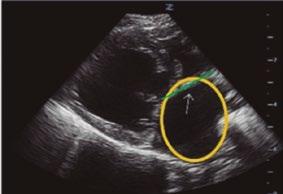

Utilidad clínica de la ecografía pulmonar y cardiaca en urgencias